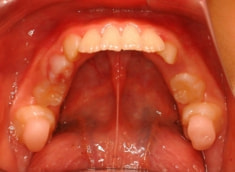

上顎の劣成長が顕著なので、上顎犬歯の萌出するスペースが不足しています。

また、統計通り、左上の犬歯です。

リケッツ分析の統計上、男児は18才まで顔面の成長があるので、それまで経過観察を行いました。

外科矯正も回避できて、さらに非抜歯で本格矯正を行うことができると診断し、現在2期治療中です。